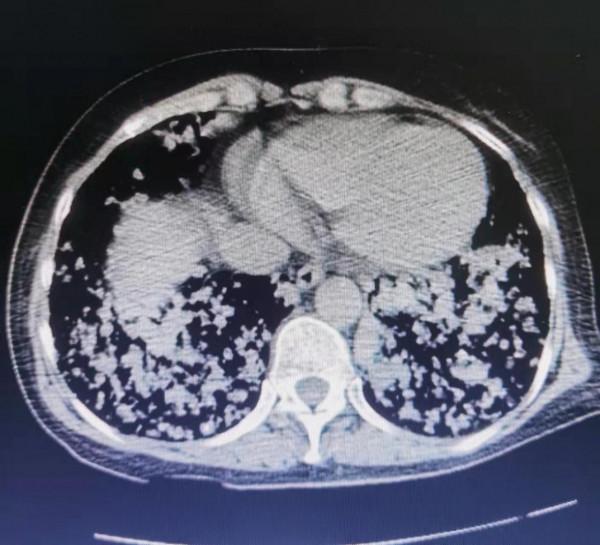

看到這個病人的胸部CT影象,我驚呆了,從醫這麼多年,真的沒見過這麼恐怖的影象,整個肺部就像滿布的雪花,又像蜂巢一樣千瘡百孔。可以說殘存的正常肺組織很少,全部被腫瘤佔據了。然而更為嚴重的是,腫瘤已經侵犯浸潤到氣管,她的氣管狹窄變扁,而咳血和氣喘主要也是由於氣管這裡的病變引起的。

這是這個病人的肺部CT:

這個病人是11年前患甲狀腺濾泡癌,當時做了甲狀腺部分切除手術,術後前兩年複查沒有太大問題,之後再也沒去過醫院,自己服用不清楚什麼成分的偏方,半年前就發現幹活之後氣喘,一直拖著沒去看,這次是咳血了才想起來到醫院檢查,這個肺部的影象屬實把大家都咋了一跳,“千瘡百孔”來形容一點不為過。這就是典型的肺轉移癌。這個病人已有呼吸衰竭的表現,需要立即吸氧,最後趕緊讓其到急診搶救。